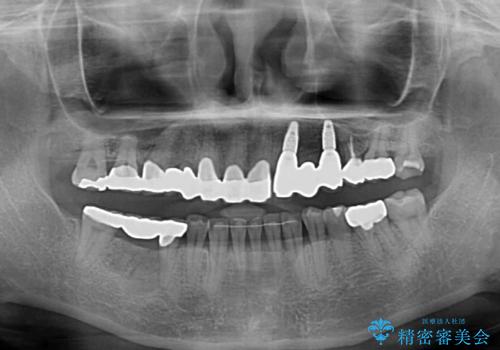

- 割れていると言われて放置してしまった歯や、前歯のデコボコなどが気になるとのことで来院された患者様です。

左上の歯は割れてしまっており、抜歯のうえインプラント治療が必要であり、他にも抜歯の必要な歯がある状態でした。

上顎はほぼ全ての歯をセラミッククラウンにて補綴治療を行う必要があるため、気になるデコボコや深い咬み合わせを改善するために下顎と上顎の臼歯部の矯正治療を行うこととしました。

並行して左下にはインプラントを埋入し、矯正治療を終えると同時に補綴治療を行うこととしました。

過蓋咬合(下顎前歯が隠れてしまうほどの深い咬み合わせ)のため、スムーズに歯が動かず矯正治療に時間がかかりましたが、無事に仕上げることができました。